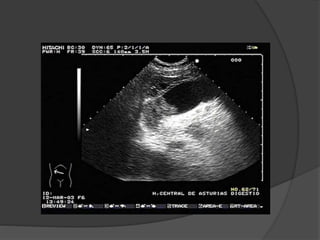

 Ecografía abdominal

 Ecografía abdominal Tomografía computarizada  Radiografía abdominal